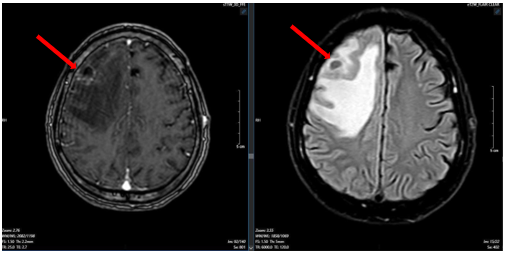

Sau 3 chu kỳ điều trị, bệnh nhân được làm lại các xét nghiệm và chụp lại kiểm tra. Kết quả cho thấy kích thước các khối u đều giảm đáng kể, thẻ hiện sự đáp ứng tốt với liệu trình điều trị của bệnh nhân

Hình 6.

Hình ảnh phim chụp cộng hưởng từ não ngày 12 tháng 07 năm 2025 (mũi tên trắng) so với ngày 25 tháng 03 năm 2025(mũi tên đỏ) cũng thể hiện kích thước khối u đã giảm đáng kể so với phim chụp cũ.